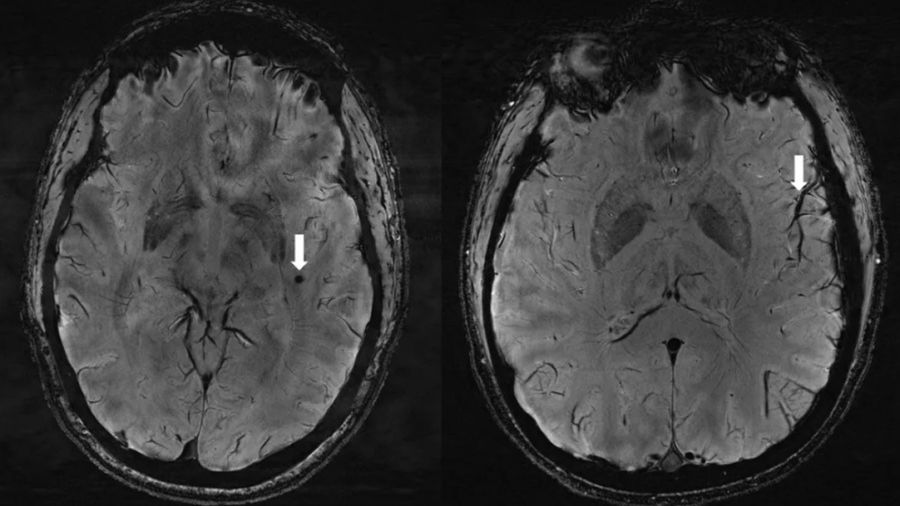

Osoby cierpiące na migrenę mają specyficzne zmiany w mózgu – wynika z nowych badań. Korzystając z rezonansu magnetycznego o ultrawysokiej rozdzielczości naukowcy odkryli, że przestrzenie okołonaczyniowe w mózgu są znacznie powiększone u pacjentów, którzy doświadczają zarówno chronicznej, jak i epizodycznej migreny. Odkrycia te mogą otworzyć nowe możliwości dalszych badań nad leczeniem tej wyniszczającej choroby.

Naukowcy z University of Southern California w Los Angeles zidentyfikowali powiększone przestrzenie okołonaczyniowe w mózgach osób cierpiących na migrenę. Przestrzenie okołonaczyniowe, zwane także jako przestrzenie Virchowa-Robina, to wypełnione płynem przestrzenie otaczające naczynia krwionośne w mózgu. Zlokalizowane są najczęściej w obszarze jąder podstawnych, w istocie białej, we wzgórzu, sródmózgowiu, móźdżku, hipokampie i wzdłuż drogi wzrokowej. Na przestrzenie okołonaczyniowe wpływa kilka czynników, w tym nieprawidłowości w barierze krew-mózg czy stan zapalny. Powiększone mogą być sygnałem wielu chorób m.in. otępienia czy nadciśnienia tętniczego oraz, jak wynika z nowych badań, odgrywają rolę także w migrenach. Pytanie tylko, czy mechanizm ten jest skutkiem czy przyczyną choroby.

- U osób z przewlekłą oraz epizodyczną migreną bez tzw. aury występują znaczące zmiany w przestrzeniach okołonaczyniowych w obszarze mózgu zwanym środkiem półowalnym. Te zmiany nigdy wcześniej nie były zgłaszane – powiedział Wilson Xu, doktorant z Keck School of Medicine na University of Południowa Kalifornia w Los Angeles, współautor badania. – Przestrzenie okołonaczyniowe są częścią systemu usuwania płynów w mózgu. Badanie, w jaki sposób przyczyniają się do migreny, może pomóc nam lepiej zrozumieć złożoność jej powstawania – dodał.

Analiza skanów MRI wykazała, że ​​liczba powiększonych przestrzeni okołonaczyniowych w środku półowalnym była istotnie większa u pacjentów z migreną w porównaniu z grupą kontrolną. Ponadto powiększone przestrzenie okołonaczyniowe w środku półowalnym korelowały z nasileniem pobudzenia istoty białej u pacjentów z migreną. - Badaliśmy migrenę przewlekłą i migrenę epizodyczną bez aury i stwierdziliśmy, że w obu typach migreny przestrzenie okołonaczyniowe były większe w środku półowalnym – powiedział Xu.